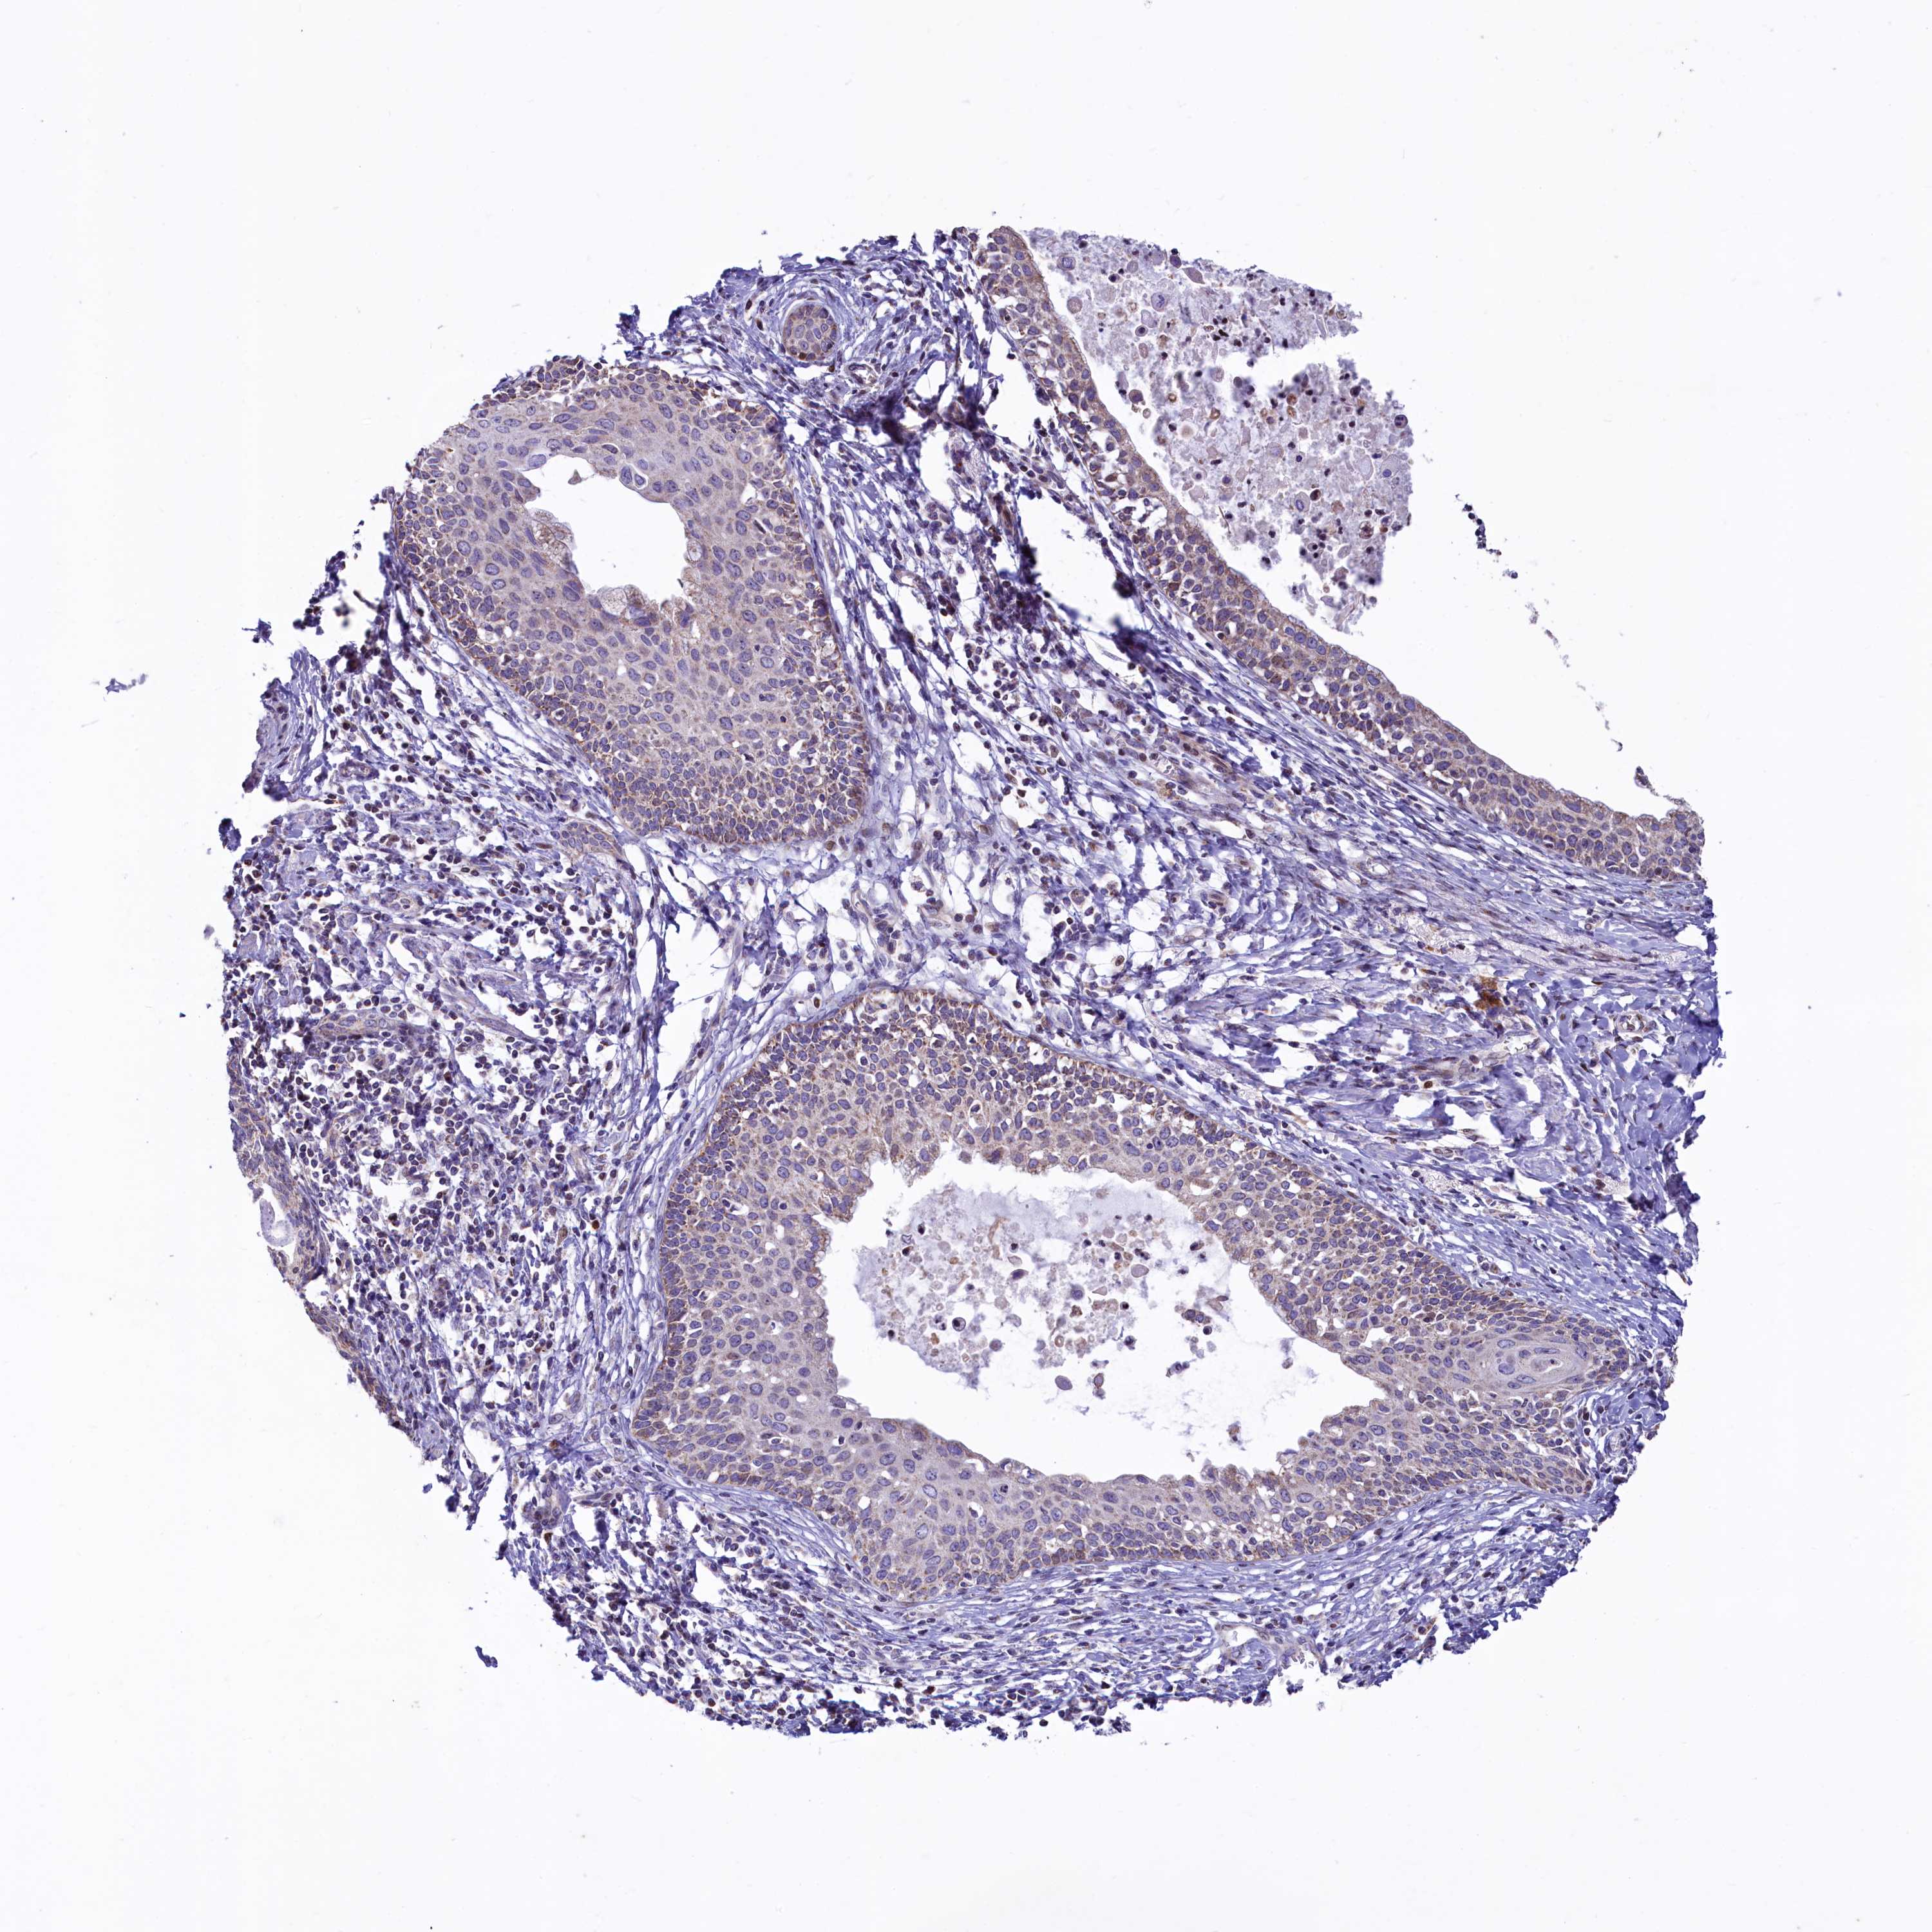

CERVICAL CANCER - Protein expressioni

A mouse-over function shows sample information and annotation data. Click on an image to view it in a full screen mode. Samples can be filtered based on level of antibody staining by selecting one or several of the following categories: high, medium, low and not detected. The assay and annotation is described here.

Note that samples used for immunohistochemistry by the Human Protein Atlas do not correspond to samples in the TCGA dataset.

Antibody stainingi

Antibody staining in the annotated cell types in the current human tissue is reported as not detected, low, medium, or high, based on conventional immunohistochemistry profiling in selected tissues. This score is based on the combination of the staining intensity and fraction of stained cells.

Each image is clickable and will lead to virtual microscopy that enables deeper exploration of all samples and also displays staining intensity scores, fraction scores and subcellular localization as well as patient and tissue information for each sample.

Antibody HPA040401

Antibody HPA043921

Staining

High

Medium

Low

Not detected

Intensity

Strong

Moderate

Weak

Negative

Quantity

>75%

75%-25%

<25%

None

Location

Nuclear

Cytoplasmic/membranous

Cytoplasmic/membranous,nuclear

Squamous cell carcinoma, NOS

Adenocarcinoma, NOS